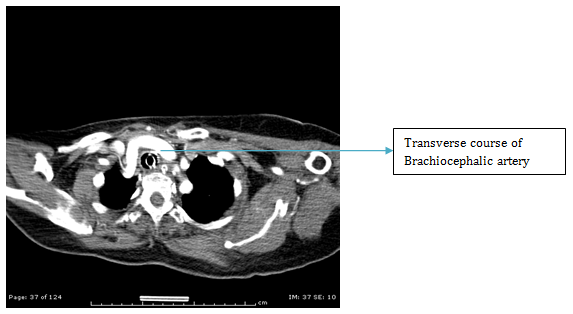

ENT referral was sought and a colour Doppler was advised which showed an abnormal large artery in running across in front of the Trachea. A CT angiography was then done which revealed anomalous Brachiocephalic trunk running from left to right across in front of the trachea which had pushed the thyroid gland to the level of Cricoid cartilage (Figures 1-4).

Literature was searched for this anomaly and it was found to be a rare anomaly (Beautiful description in an anatomy journal).4 The challenges were two: first, the surgical difficulty in view of the horizontally running large vessel in front of the trachea just 1cm below the Cricoid cartilage and second, the risk of post operative hemorrhage due to the vessel hitting against the Tracheostomy tube due to pounding pulsations, movement of the tube due to mechanical ventilation, frequent handling for suctioning and dressing and neck movements.5-7

The brachiocephalic artery (or brachiocephalic trunk or innominate artery) is an artery of the mediastinum that supplies blood to the right arm and the head and neck. It is the first branch of the aortic arch, and soon after it emerges, the brachiocephalic artery divides into the right common carotid artery and the right subclavian artery. There is no brachiocephalic artery for the left side of the body. The left common carotid and the left subclavian artery, come directly off the aortic arch. However, there are two brachiocephalic veins. It arises, on a level with the upper border of the second right costal cartilage, from the commencement of the arch of the aorta, on a plane anterior to the origin of the left carotid; it ascends obliquely upward, backward, and to the right to the level of the upper border of the right sternoclavicular articulation, where it divides into the right common carotid and right subclavian arteries. The artery then crosses the trachea in front of it obliquely from the left to the right, roughly at the middle of the trachea or the level of the ninth tracheal cartilage.

In vascular anomalies as in our case, open tracheostomy is safer compared to percutaneuous tracheostomy to minimize the risk of bleed during procedure but also to undertake reconstructive measures to prevent the late complication of erosion of major vessels. This anatomical variation in which the Brachiocephalic artery is overlying the trachea where incision for tracheostomy is made or the guide wire of the PDT is inserted we encountered is very rare and failure to identify it would have led to catastrophic complication at tracheostomy and not undertaking rotational muscle flaps during surgery would have led to post operative vascular laceration and lethal bleeding.